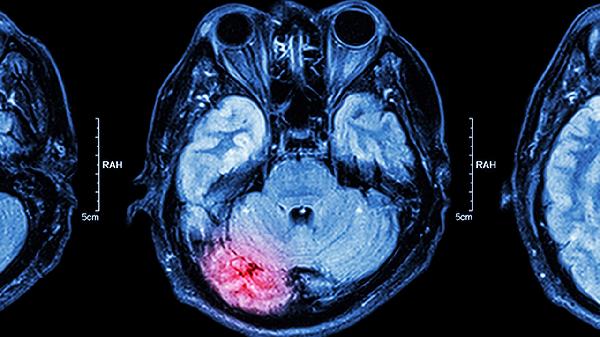

三、脑供血不足

心脑健片适用于脑供血不足引起的头晕、头痛、记忆力减退等症状。脑供血不足是指脑血管循环障碍导致脑组织缺血缺氧的状态。心脑健片中的活性成分可以改善脑部微循环,增加脑血流量。脑供血不足患者可能表现为头晕目眩、注意力不集中、睡眠障碍等,心脑健片可以帮助缓解这些症状。